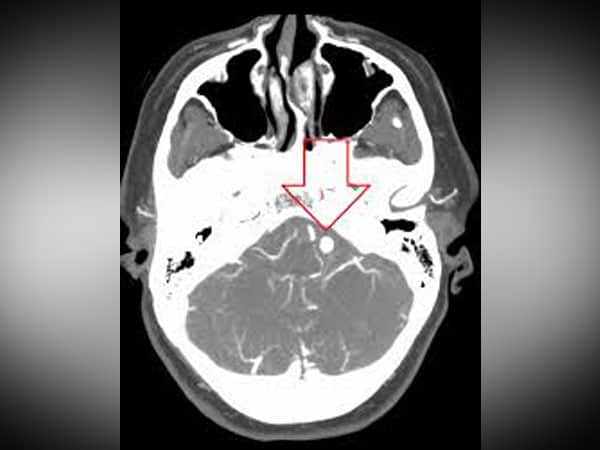

Brain aneurysms are a bulge in a blood vessel caused by a weakness in the blood vessel wall. As blood passes through the weakened blood vessel, blood pressure causes a small area to bulge outwards.

Using sophisticated ‘next generation’ DNA sequencing technologies, teams in Washington lead by Manuel Ferreira, identified a new genetic basis of a form of a brain aneurysm (mutations PDGFRB). This was unexpected, as mutations in this gene have been previously identified in completely different human developmental disorders.